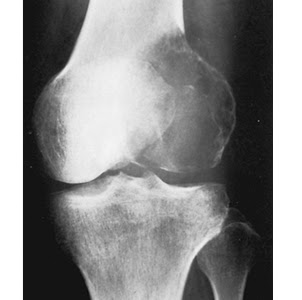

This benign lesion has a predilection for the epiphyses and apophyses.

What is a chondroblastoma?

The typical age range for this painful lesion involving the metaphysis and epiphysis.

What is 20-40?